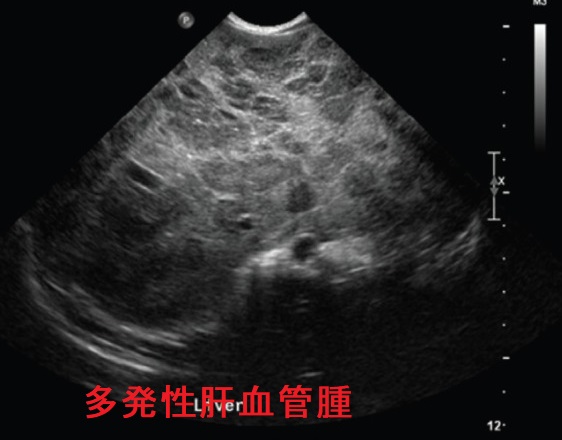

肝血管腫で甲状腺機能低下症

甲状腺乳頭癌の全身転移を検索するためのDWIBS(ドゥイブス) で、偶然見つかった肝血管腫